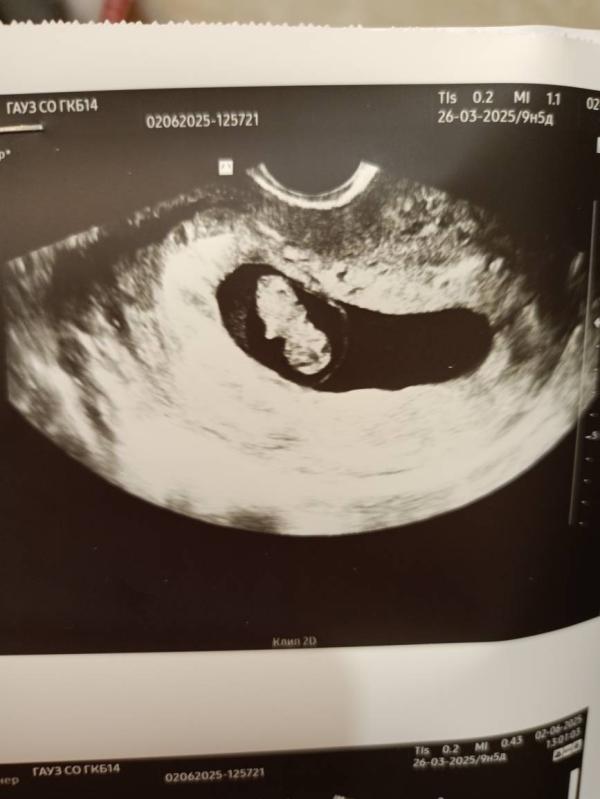

В понедельник 2ого июня я была на УЗИ и на приеме.

Начну пожалуй с УЗИ ( это было мое второе УЗИ, первое было на сроке 4-5 недель , тогда я только узнала о тебе и на следующий же день поехала на первое УЗИ 😅

По узи всё хорошо, срок беременности 9.1 день по малышу🤰Ручки и ножки только образовываются, скоро он будет полноценным человечком😍( Расти малыш!). Малыш прекреплен по задней стенке , я уверена, что он мальчик , сынок!

На фото второе и первое узи❤🔥